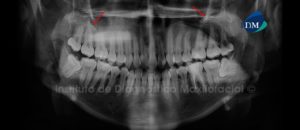

Paciente de sexo femenino de 32 años de edad acude al Instituto de Diagnóstico Maxilofacial para evaluación general de ambos maxilares. A la evaluación panorámica